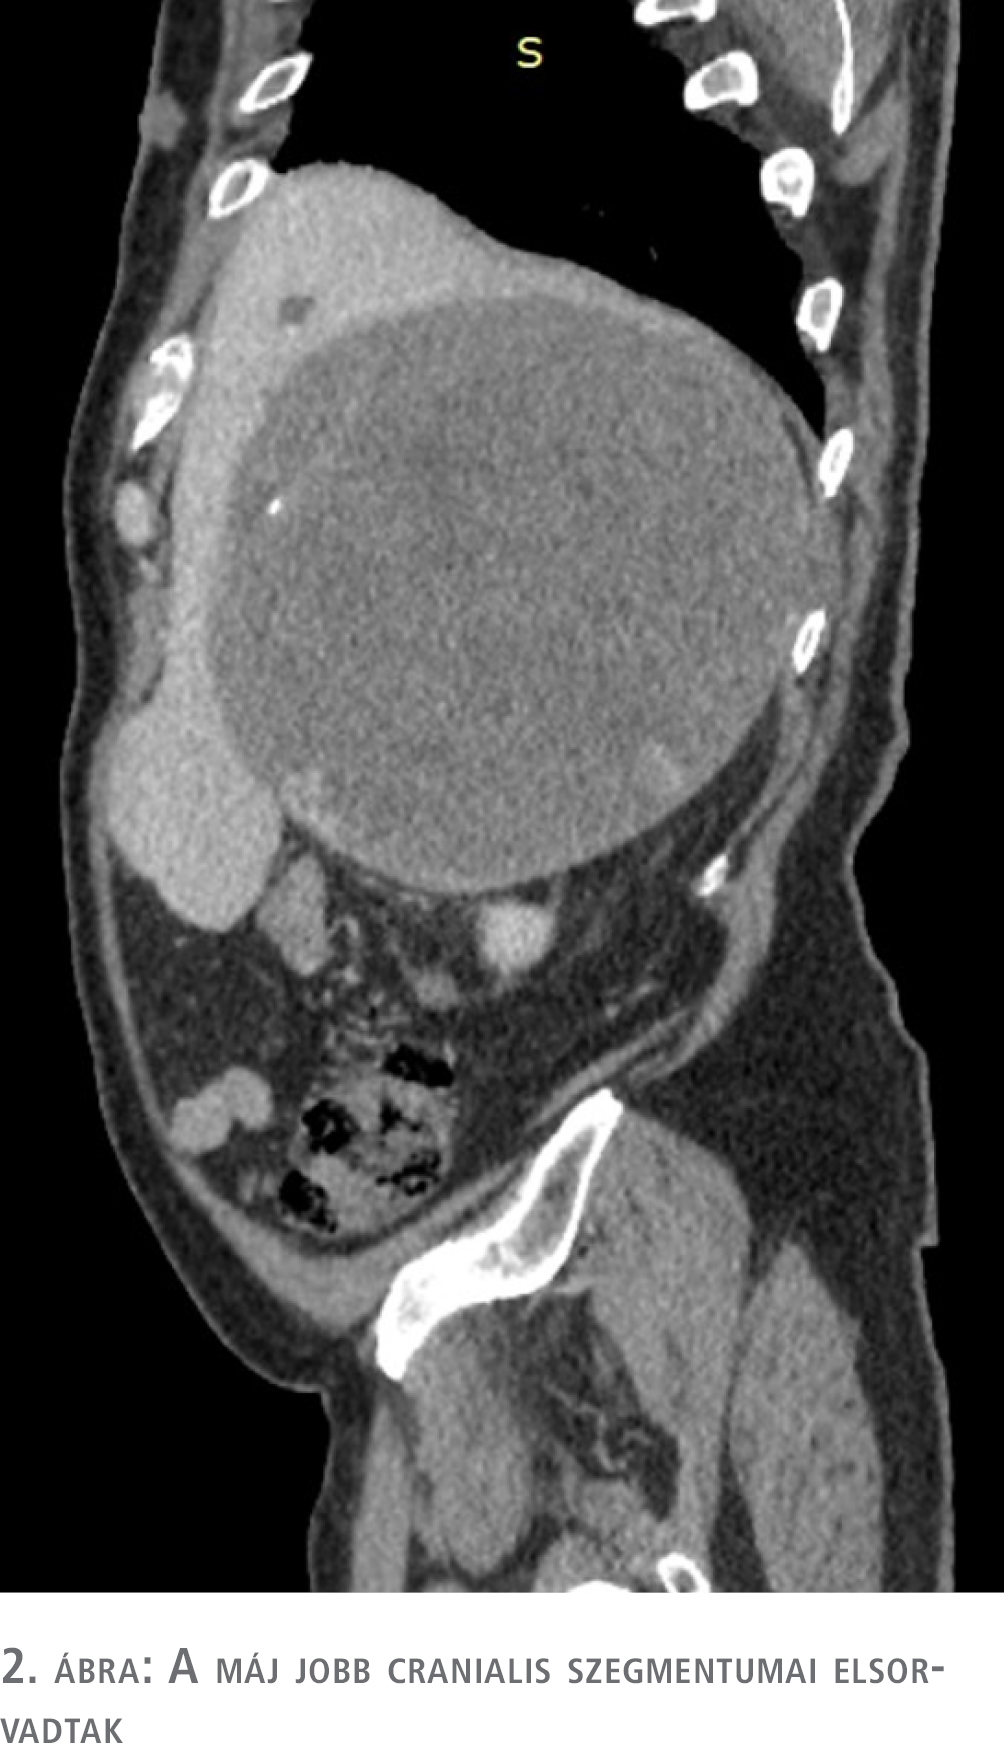

Hasi ultrahangvizsgálat során a máj jobb lebenyének vetületében 16 cm-es inhomogén képletet észleltek, amelynek pontosabb megítélése végett ambuláns CT-vizsgálatot javasoltak. Az elvégzett CT bizonytalan eredetű (máj- és mellékvese-eredetet is felvetett) és malignitású, 18 cm legnagyobb átmérőjű, szélein halmozó, meszesedéseket is tartalmazó képletet írt le.

A CT eredménye alapján a szakrendelőből a beteget sürgősséggel az endokrinológiai osztályra utalták további kivizsgálás céljából. Az endokrinológiai osztályos kivizsgálás során ismét CT-vizsgálatot végeztek, amely a térfoglalás májeredetét elvetette, és halmozási dinamikája alapján elsősorban adrenocorticalis carcinomának véleményezte (1–4. ábra). A hormonprofil alapján hormontermelésre utaló eltérés nem igazolódott. ACTH-, DHEA-S-, kortizol-, CgA- és vizeletmetanefrin-szintek meghatározása, valamint negatív eredményű dexametazonszuppressziós teszt történt. A vizsgálatok és a klinikai kép alapján hormontermelő tumor nem igazolódott. Biopsziát nem végeztek, tekintve, hogy terápiás konzekvenciája nem lett volna sem malignus, sem malignitás nélküli eredmény esetén: a terime mérete alapján malignitási potenciálja nagy, ily módon műtéti ellátása csak malignusnak tekintve történhet.

A máj balra diszlokálódott, a jobb cranialis szegmentumai elsorvadtak, a térfoglalás a vena cava inferiort felemelte és komprimálta, a vesét caudalis irányba diszlokálta. A máj mobilizálása után a terime fluktuáló részletéből intraoperatív citológiai mintát küldtünk, amely a vérből alakos elemeket és kevés histiocytát tartalmazott, így malignitást sem kizárni, sem megerősíteni nem tudtunk, így a térfoglalást továbbra is potenciálisan malignusnak tekintve, onkológiai-sebészeti elvek alapján in toto eltávolítás mellett döntöttünk (6. ábra).